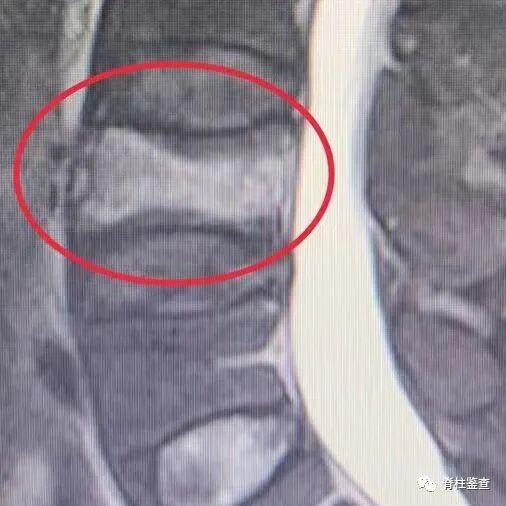

腰4骨质疏松性骨折

骨质疏松性椎体骨折Kümmell病

骨质疏松性椎体骨折:椎体部分塌陷